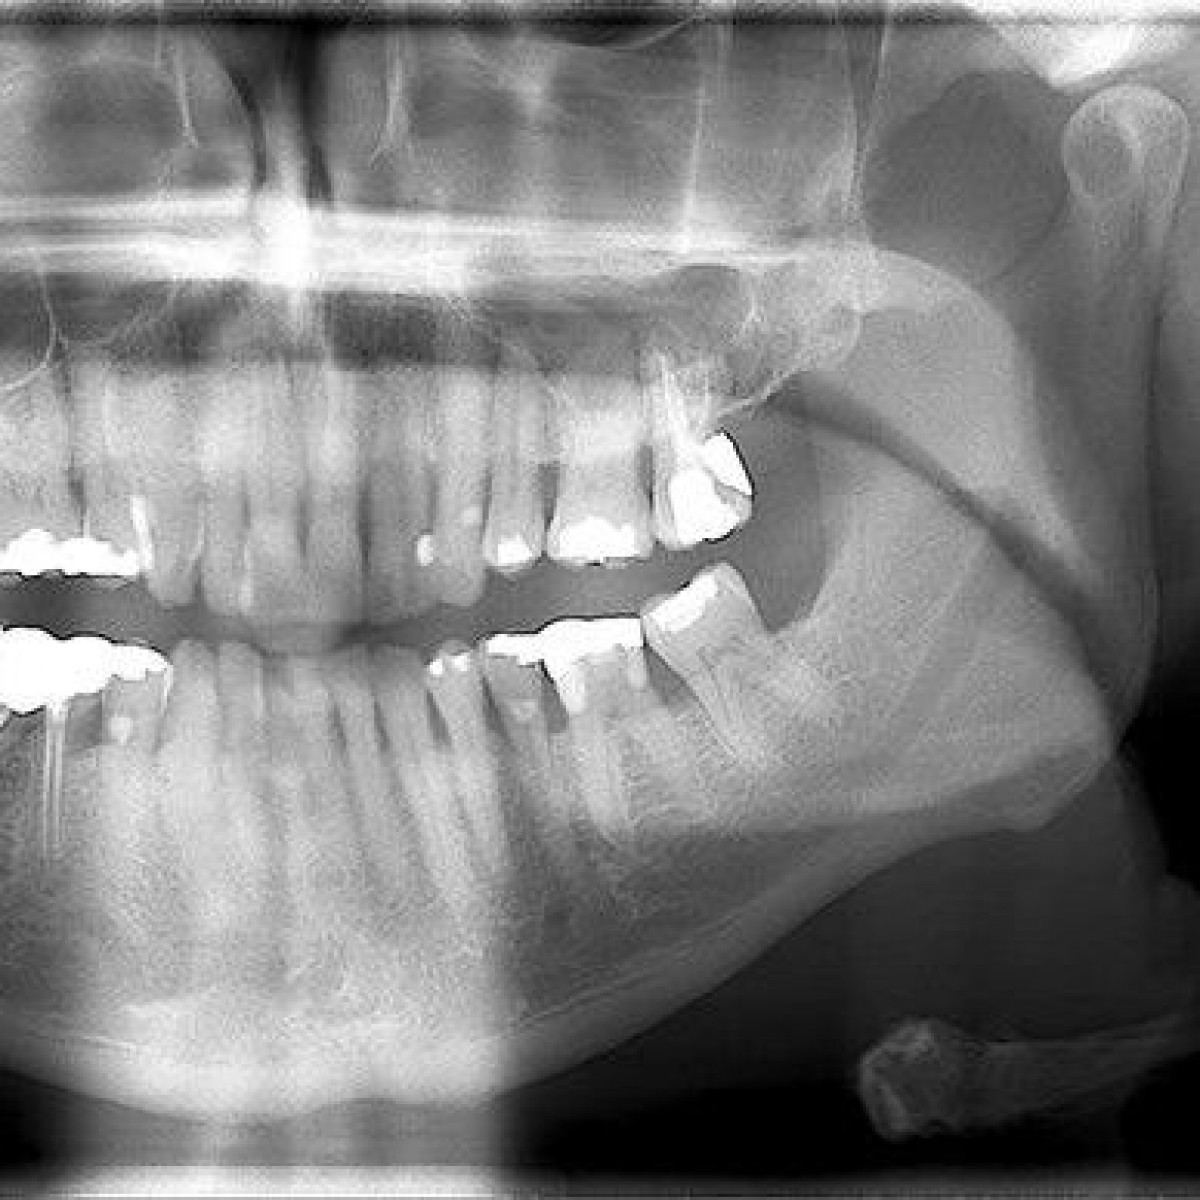

In this case series, we documented the treatment of three male patients who were referred for further investigation of well-defined, corticated radiolucent lesions. Two lesions were located in the body of the mandible and one in the anterior maxilla. All three patients were in their fifth decade of life. Two patients reported mild discomfort, while one patient was asymptomatic upon presentation.

The included cases were treated conservatively with enucleation and curettage under general anaesthesia. Histological examination confirmed a diagnosis of GOC in all cases. No clinical or radiographic recurrence has been observed.

The clinical, radiographic and histological appearance of the GOC mimics other cysts and tumours of the jaw, most significantly central mucoepidermoid carcinoma. Long-term follow-up is recommended due to the potential for recurrence, which is influenced by lesion size, locularity and cortical plate integrity.